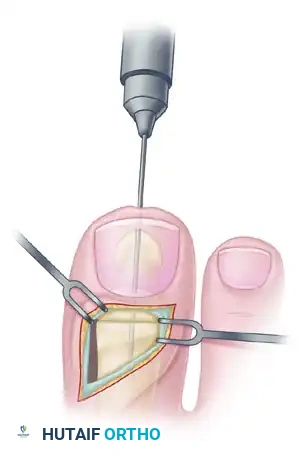

Step 3: Preparation for Interphalangeal Joint Arthrodesis

With the EHL detached, the IP joint is easily accessed.

- Perform a transverse arthrotomy of the IP joint.

- Acutely flex the distal phalanx to expose the articular surfaces of both the head of the proximal phalanx and the base of the distal phalanx.

- Using a microsaw or rongeur, resect the articular cartilage down to bleeding subchondral bone. The cuts should be flat and parallel to permit a neutral position in both the sagittal and coronal planes.

Step 4: IP Joint Fixation (Shives and Johnson Technique)

Rigid internal fixation is paramount for a successful arthrodesis. The use of a 4.0-mm cancellous lag screw, as advocated by Shives and Johnson, provides excellent compression and rotational stability.

- Retrograde Drilling: Drill a 2.0-mm diameter hole longitudinally in a retrograde manner starting at the center of the denuded articular surface of the distal phalanx.

- The drill bit should exit the skin at a point exactly 5 mm plantar to the tip of the nail in the midline of the toe.

- Antegrade Drilling: Appose the denuded articular surfaces of the proximal and distal phalanges in neutral alignment. Insert the drill bit distally at the tip of the toe (through the previously created exit hole) and advance it proximally.

- Follow the previously placed retrograde hole, cross the IP joint, and drill into the base of the proximal phalanx, advancing down the center of its medullary canal.

- Overdrilling and Tapping: To achieve a true lag effect, overdrill the distal phalanx (the near cortex) with a 2.7-mm drill bit to create a gliding hole. Tap the entire drill path with a 3.5-mm tap to prepare for the cancellous screw.

- Screw Insertion: Following the drill path in a proximal direction, insert a 4.0-mm partially threaded cancellous bone screw.

- As the screw head engages the distal phalanx, the lag effect will produce robust compression across the arthrodesis site, ensuring firm fixation.